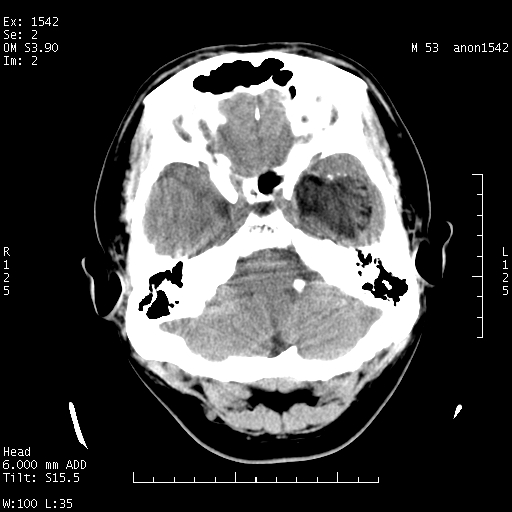

标题: CT10811:M53Y,头痛一月.其它没有什么 [打印本页]

左侧鞍旁不规则低密度,此区域和侧脑室有液平。若无外伤史。考虑左侧鞍旁表皮样囊肿自发破溃。

鞍旁颞叶低密度灶.其中散在空气影.还有侧脑室.是否考虑脑脓肿(请提供病史情况)

有肿瘤样病变破溃,沿外侧裂生长,为什么不考虑胆脂瘤?

1 囊性肿物. 2 请楼主上传介少病人资料. 3 表皮样囊肿或胆脂瘤都在考虑范围内,确切的不知ct值是多少.4了解病史后在缺定.